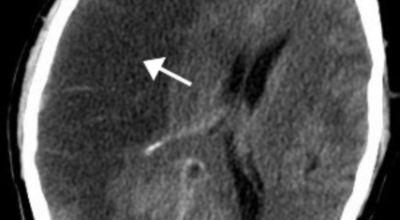

뇌출혈이란 뇌혈관의 출혈이 원인이 되어 일어나는 뇌혈관장애, 뇌일혈이라고도 그러나, 이는 갑작스러운 의식 장애, 이완성 반신불수 등을 유발하는 뇌졸중을 유발하는 대표적인 질환이예요. 뇌출혈의 대부분의 원인은 고혈압증이 원인이지만 드물게 백혈병이나 재생불량성 빈혈 과 같은 혈액질환과 함께 종양, 외상, 매독 등이 원인이 됩니다.

고혈압성 뇌출혈의 원인은 고혈압만이 아니라 터지기 쉬운 상태의 혈관에도 있다고 생각이 가능하지만, 아직까지 발생병리는 완전히 해명이 되지 않은 상태예요. 현재 생각 되는 것은 뇌내세 소동맥, 보통과 다르게 분기부의 혈관벽에 변화가 일어나서 연약해진 곳이 내압을 이겨내지 못하고 팽배해서 터져서 출혈을 한다는 것이죠. 뇌출혈이 일어나는 장소는 내포 부근이 가장 많다고 하며 이 부분의 중대뇌동맥의 가지가 터져서 출혈해요.

뇌출혈은 발작 직후 안정을 취해야 해요. 뇌부기를 가라앉히기 위해 약물 요법으로 고농도 포도당, 덱사메타존, 만니톨 등을 투약할 수 있고 뇌의 혈액 순환을 회복시키는 주사와 지혈제, 진정제 등을 활용할 수 있답니다. 혈종의 크기가 중등도 이상으로 마비 증세가 있다면 머리뼈에 작은 구멍을 내서 관을 넣어 혈종을 뽑아내는 수술을 시행할 수 있습니다.

혈압성 뇌출혈인 경우 혈종의 크기가 작으며 환자의 증상이 경미하면 약물 치료를 시행해요. 혈종의 크기가 아주 크며 뇌가 심하게 부어오를 때는 응급으로 머리뼈를 절개해 혈종을 빠르게 제거해야해요. 응급조치가 늦어지면 뇌압이 상승해 의식을 잃고 사망에 이를 수 있기 때문인데요 이렇게 증상이 심할 때는 수술이 잘 되었더라도 예후가 좋지 못할 때가 많다고 해요.